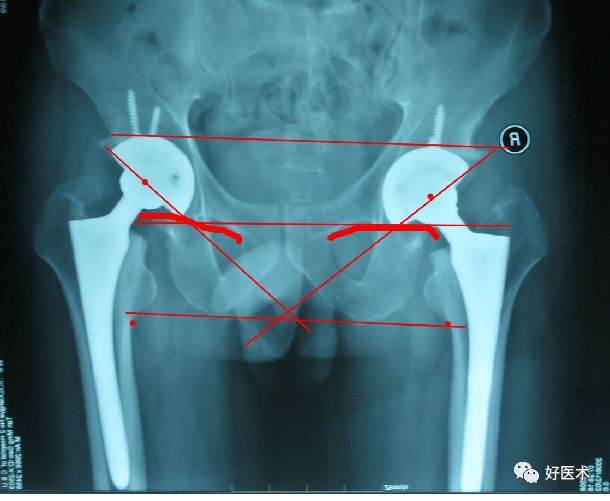

髋关节X线评估:

X-rays

-

骨盆前后位

蛙式位

Cross –table位

在拍摄X线片前须确保合适的技术

放大率

术后评估内容:

1、髋臼假体:泪滴、沈通氏线、外展角、前倾角、髋臼旋转中心。

2、股骨假体:颈干角、前倾角、柄-髓腔比

3、假体-骨界面;假体-骨水泥界面;骨水泥-骨界面

4、双下肢等长

髋臼假体:

1 外展角:45°±10°

2 沈通氏线连续

3 髋臼窝应将假体包容

(≥70%)

4 下肢实际长度最好维持10mm以内。

前倾角:15°±10°

正位片上不能区分出前倾或后倾.必须根据侧位片决定。

股骨假体:

柄-髓腔轴线夹角

通过正位X 线片上测量假体柄长轴与股骨长轴间夹角来确定, 夹角≤3°为中心固定。

超出3°为内翻或外翻固定:

远端尖端在外侧-内翻;

远端尖端在内侧-外翻

柄-髓腔比

分别在正位和侧位X 线片上, 在三个水平( 小转子上缘、柄的中部、柄尖端近侧1 cm) 检测假体宽度与髓腔宽度之比(B/A×100%) 来确定。

正位片上>80%, 侧位片>70%为匹配满意。

前倾角:10°-15°

必须由侧位片评估。

注意:部分假体自带前倾角,术中应予注意,以免术中再前倾放置引起前倾过度。

假体的理想位置

髋臼外展角在40°-55°之间

前倾角在10°-20°之间

尽可能将髋臼假体放置于髋臼的解剖的位置上

术中应冲减或适当增大股骨偏心距

尽量将股骨柄假体置于中立位